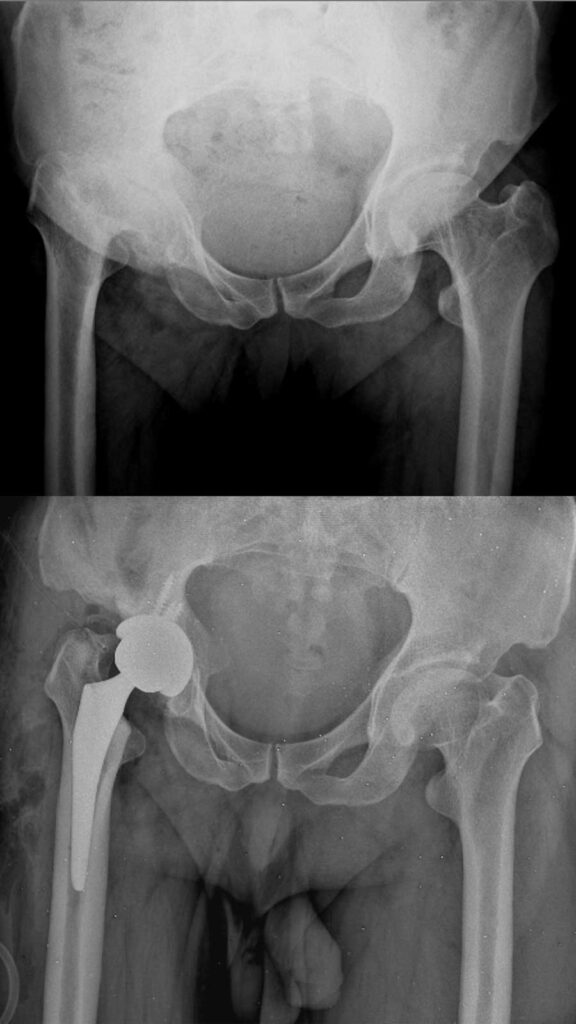

عکس تعویض مفصل لگن

برای آشنایی با تصاویر واقعی رادیوگرافی لگن قبل و بعد از جراحی، عکس تعویض مفصل لگن چند بیمار در زیر وجود دارد. با کلیک بر روی هر کدام از آنها تصویر بزرگتر و کامل را خواهید دید.